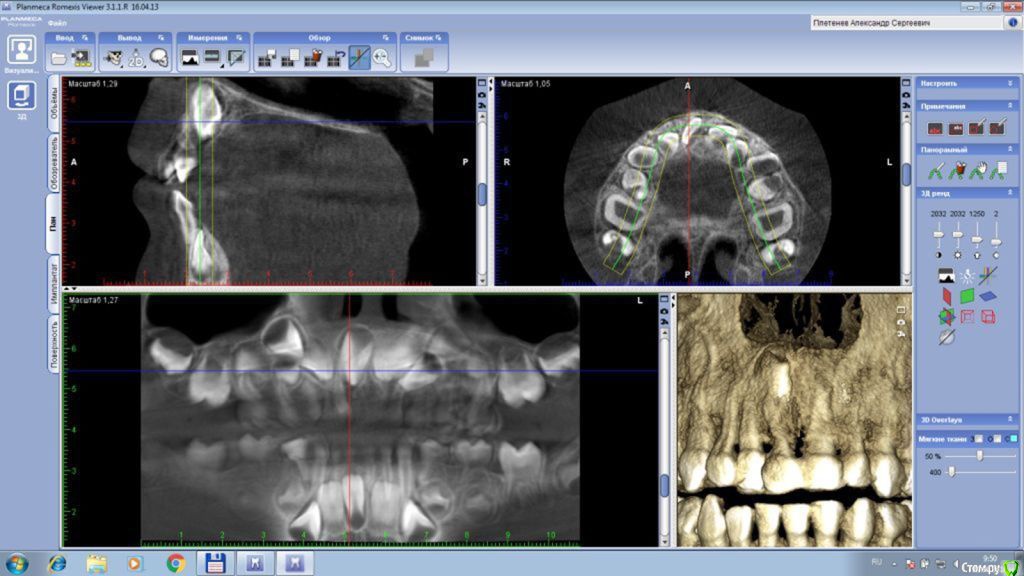

В 5,5 лет сделали 3D снимок, на котором видно, что всего три зачатка коренных зубов между нижними резцами.